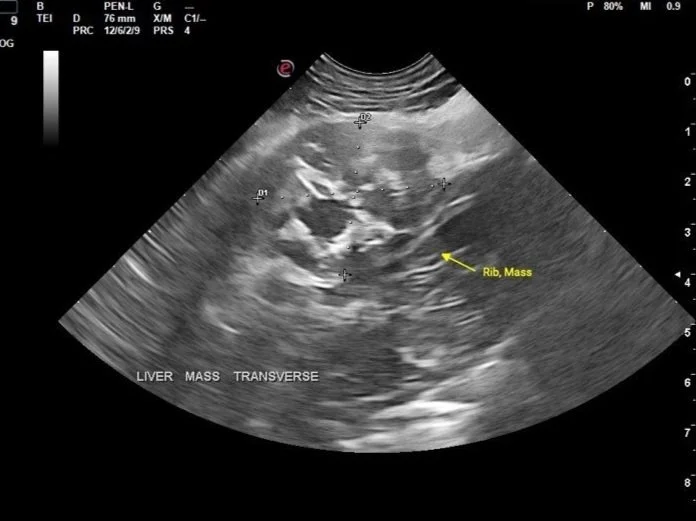

Case of the Month Featured Jan 9, 2025 Suspected Renal Dysplasia in a young dog Jan 9, 2025 Sonographer: Meredith Adams, DVM Jan 9, 2025 Dec 5, 2024 Incidental Abdominal Mass Dec 5, 2024 Sonographer: Emily Evans, DVM Dec 5, 2024 Nov 1, 2024 Ultra Rare Pancreatic Disease in Cats Nov 1, 2024 Sonographer: Mallory Repellin DVM Nov 1, 2024 Oct 8, 2024 Suspected Carcinomatosis in a Feline Oct 8, 2024 Sonographer: Kara Woody DVM Oct 8, 2024 Sep 19, 2024 Lameness in a Dog Sep 19, 2024 Sonographer: Anne Desrochers DACVIM Sep 19, 2024 Jul 31, 2024 Ruff Findings: Uncovering a Rib Mass in a Juvenile Dog Jul 31, 2024 Sonographer: Danny Laderberg DVM Jul 31, 2024 Jul 3, 2024 Thyroid Carcinoma in a Canine Jul 3, 2024 Sonographer: Meredith Adams DVM Jul 3, 2024 May 30, 2024 Pituitary Dependent and Adrenal Dependent Hyperadrenocorticism in Two Littermates May 30, 2024 Sonographer: Emily Evans BVM&S May 30, 2024 May 1, 2024 Gastrointestinal Adenocarcinomas in a Feline May 1, 2024 Sonographer: Mallory Repellin DVM May 1, 2024 Mar 27, 2024 March’s Case of the Month - 2024 Mar 27, 2024 Sonographer: Kara Woody DVM Mar 27, 2024 Feb 28, 2024 February's Case of the Month- 2024 Feb 28, 2024 Sonographer: Anne Desrochers, DACVIM Feb 28, 2024 Feb 1, 2024 January's Case of the Month-2024 Feb 1, 2024 Sonographer: Danny Laderberg, DVM Feb 1, 2024 Dec 28, 2023 December’s Case of the Month-2023 Dec 28, 2023 Sonographer: Meredith Adams, DVM Dec 28, 2023 Nov 30, 2023 Novembers Case of the Month-2023. Nov 30, 2023 Sonographer: Emily Evans DVM Nov 30, 2023 Nov 1, 2023 October's Case of the Month - 2023 Nov 1, 2023 Sonographer: Mallory Repellin DVM Nov 1, 2023 Sep 27, 2023 September's Case of the Month - 2023 Sep 27, 2023 Sonographer: Kara Woody DVM Sep 27, 2023 Aug 30, 2023 August's Case of the Month - 2023 Aug 30, 2023 Sonographer: Anne Desrochers DACVIM Aug 30, 2023 Aug 3, 2023 July's Case of the Month - 2023 Aug 3, 2023 Sonographer: Meredith Adams, DVM Aug 3, 2023 Jul 6, 2023 June's Case of the Month! Jul 6, 2023 Sonographer: Emily Evans, BVM&S Jul 6, 2023 Jun 7, 2023 May's Case of the Month - 2023 Jun 7, 2023 Sonographer: Mallory Repellin, DVM Jun 7, 2023 Apr 26, 2023 April's Case of the Month - 2023 Apr 26, 2023 Sonographer: Kara Woody, DVM Apr 26, 2023 Mar 29, 2023 March's Case of the Month - 2023 Mar 29, 2023 Sonographer: Anne Desrochers, DACVIM Mar 29, 2023 Mar 1, 2023 February's Case of the Month - 2023 Mar 1, 2023 Sonographer: Meredith Adams, DVM Mar 1, 2023 Feb 1, 2023 January's Case of the Month - 2023 Feb 1, 2023 Sonographer: Dr. Emily Evans Feb 1, 2023